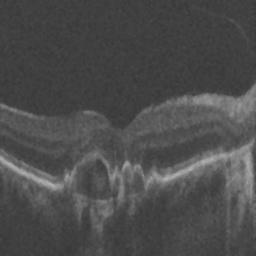

The qualitative results of the proposed system is shown in the Fig. 3. The detection task is evaluated using Area Under the Curve(AUC) metric and the segmentation task is evaluated using Dice Coefficient(DC) metric and the results are presented in Table1

| (a) De-noised OCT slice | (b)Predicted fluid region | (c)Manual fluid segmentation |

| (d) De-noised OCT slice | (e)Predicted fluid region | (f)Manual fluid segmentation |

| (g) De-noised OCT slice | (h)Predicted fluid region | (i)Manual fluid segmentation |

| (j) De-noised OCT slice | (k)Predicted fluid region | (l)Manual fluid segmentation |

| (m) De-noised OCT slice | (n)Predicted fluid region | (o)Manual fluid segmentation |